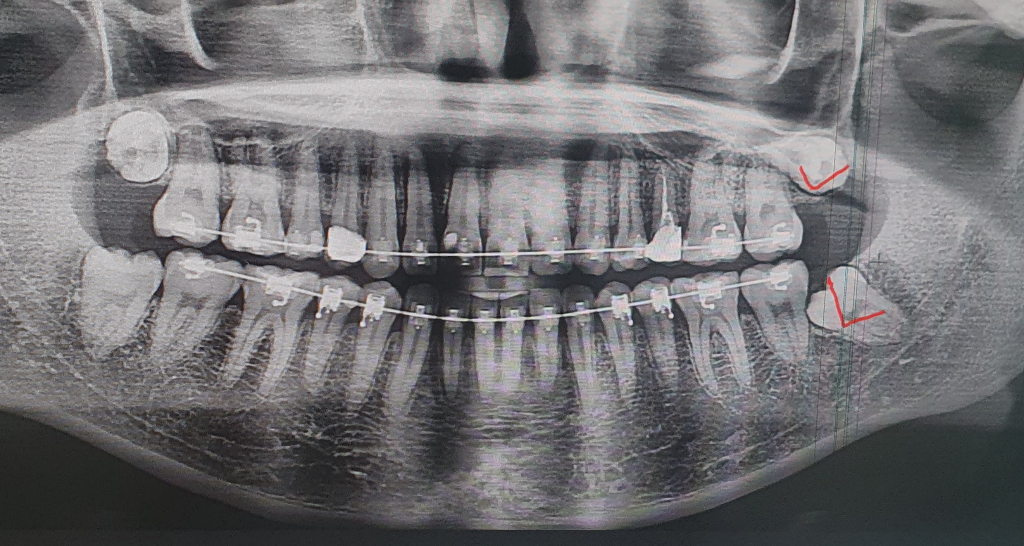

안ㄴㅕㅇ하세요! 제가 지난주에 치아 교정때문에 다른지역에가서 왼쪽아래사랑니를 뽑았는데 나머지 3개를 동시에 발치할수있을까요?

원래 왼쪽위아래뽑으려고 마츄ㅣ까지 다했는데 선생님이 아래꺼만뽑아주고 담주에오라고하더라구요 일빼는것도 어렵고 왕복 2시간이나 가야햐서 이번에 가서 같이 뽑아달라고 하면 어려울까요?? ㅠㅠ 아니면 상악 양쪽이라도 빼는게 어려울까요? 어려운 케이스인가요?

위의 양쪽 사랑니 다 깊이 매복되어 있어 국소마취로 하기 어려울 수도 있습니다. 저 정도 깊이 묻힌 것은 입원하여 전신마취 까지 해야 할 수도 있어 미룬 것으로 추정됩니다. 일단 아래 사랑니만 뽑기를 추천합니다.